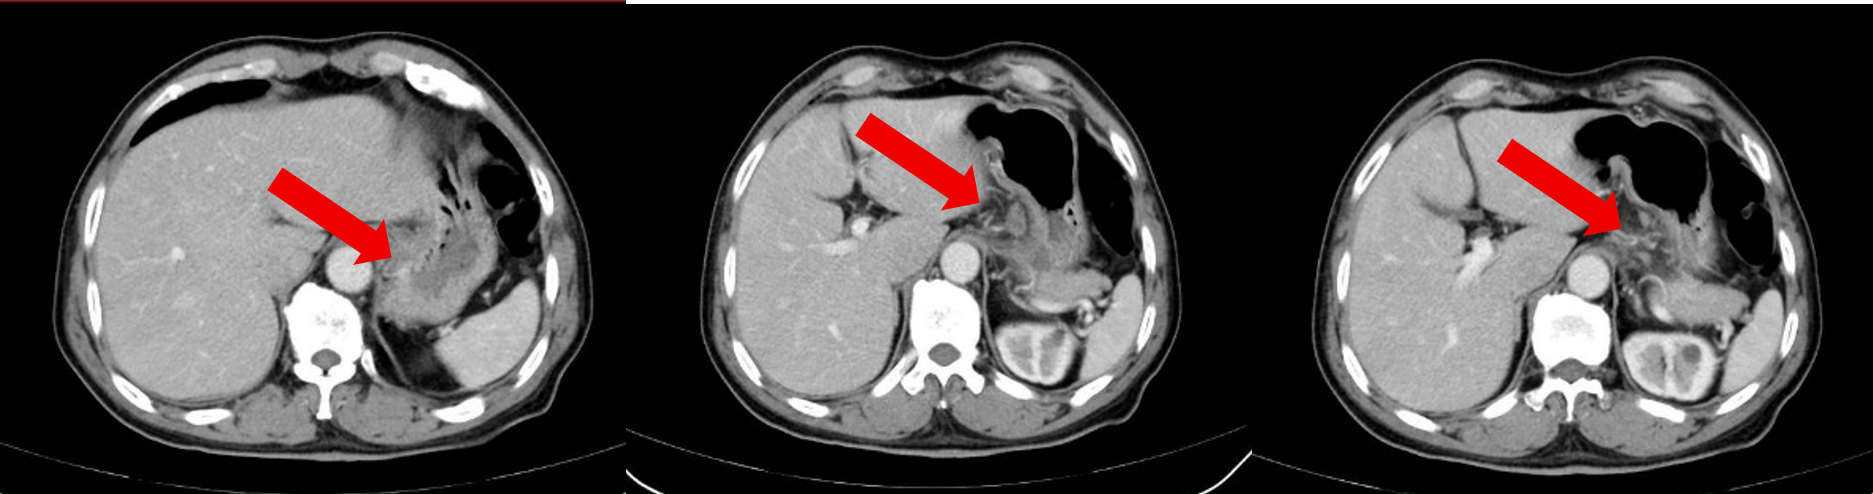

治疗6周期后患者于2025-3-6复查腹部CT:胃底、胃体小弯侧胃壁不均增厚,与邻近贲门分界不清,较前大致类似,病灶较厚处约 1.3cm。贲门左、胃小弯及肝胃间隙数个增大淋巴结,多系转移,部分较前稍缩小,大者大小约2.6×1.5cm。

经过上述系统的评估,病灶及周围淋巴结较前明显缩小,肿瘤标志物水平均在正常范围内,无新发病灶及远处转移,整体抗肿瘤疗效评估为PR。